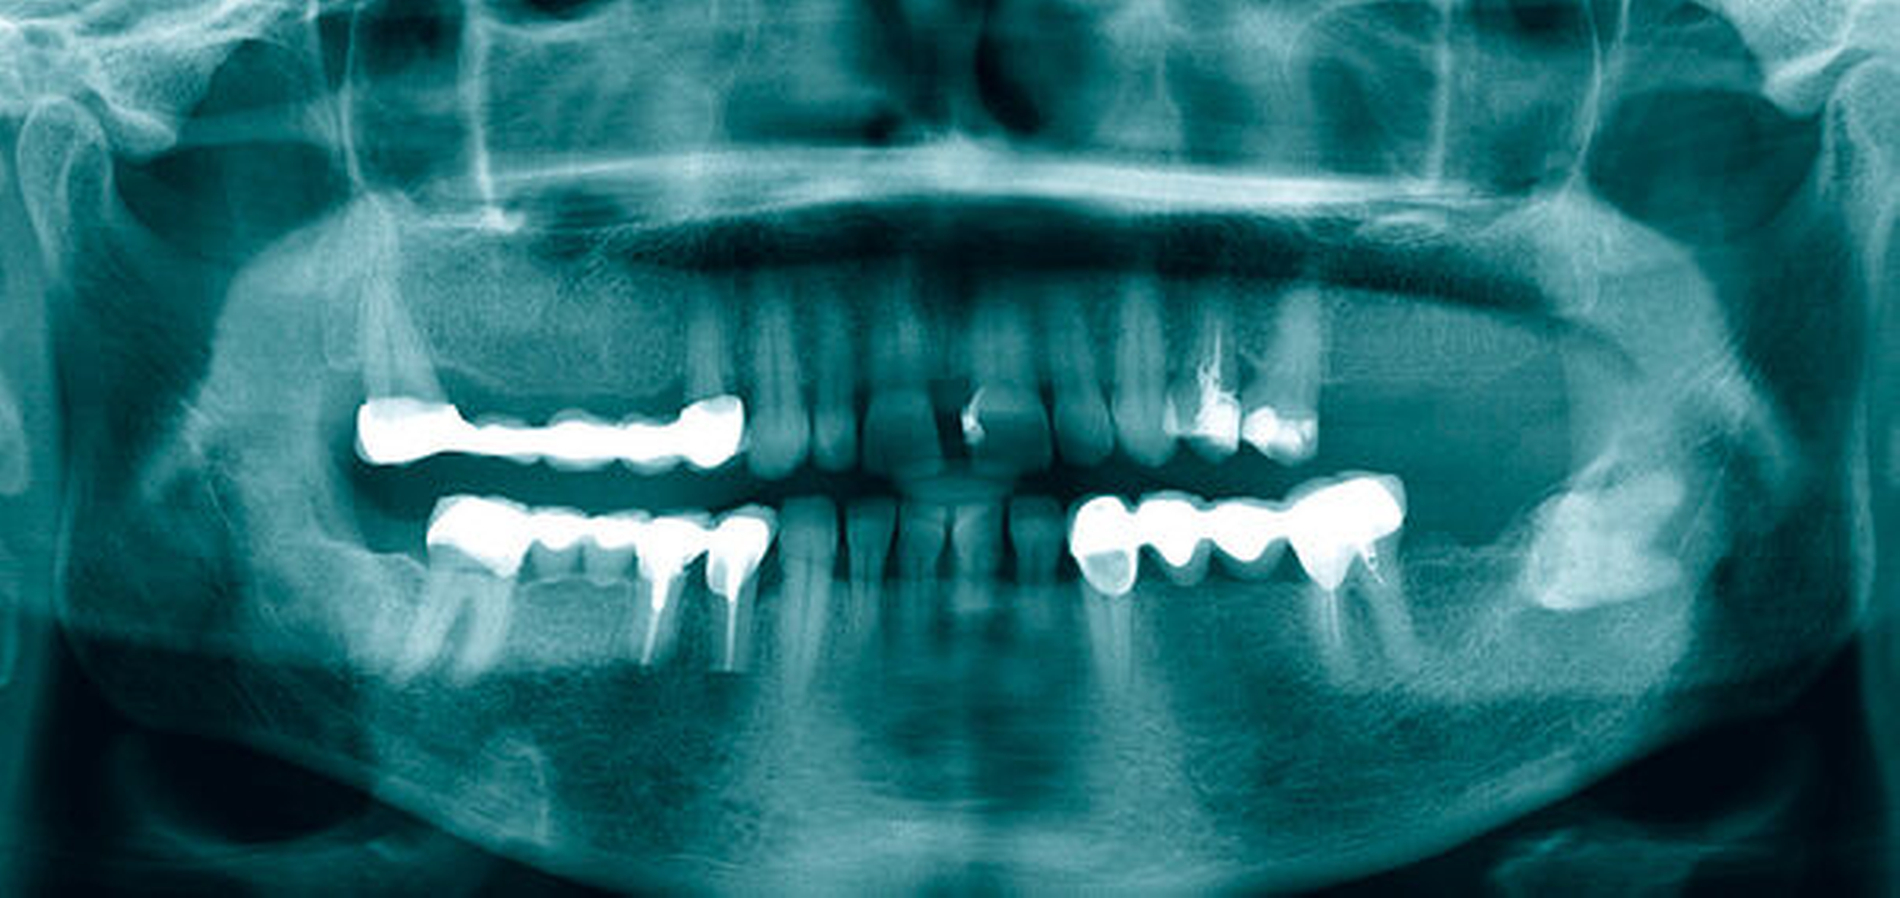

Die Labordiagnostik ergab unauffällige Befunde im Blutbild, der klinischen Chemie und Gerinnung. In der MRT-Bildgebung konnte eine 12 mm × 7 mm × 7 mm große, kontrastmittelaufnehmende Raumforderung paramandibulär links nachgewiesen werden (Abbildung 2). Insgesamt bestand somit die Indikation zur operativen Revision.